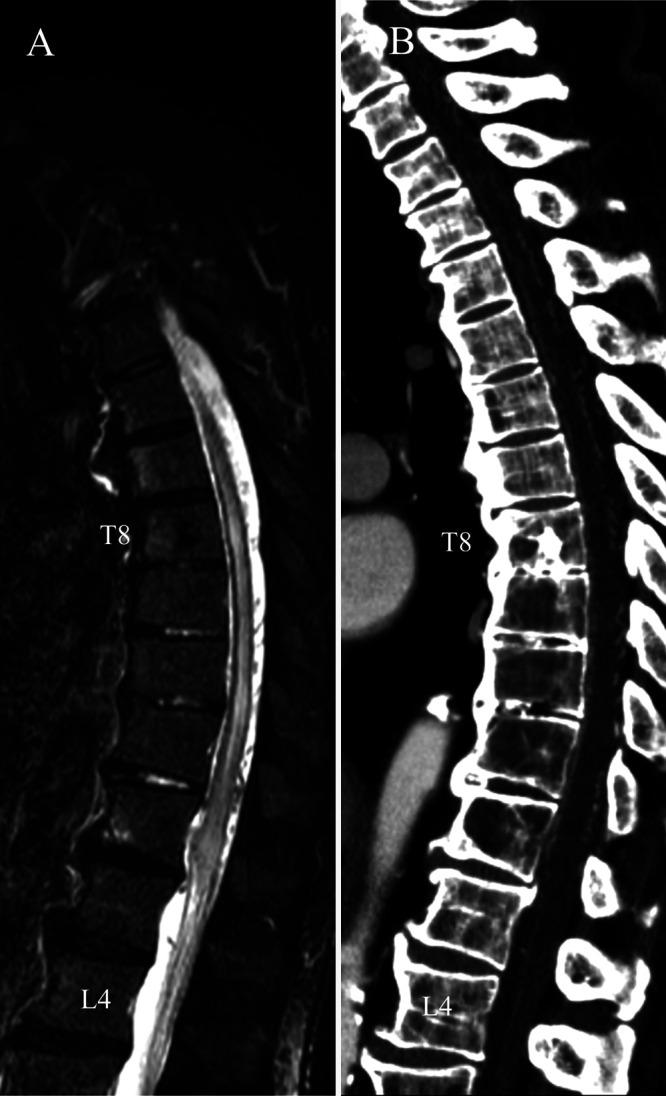

A 72-year-old man presented with progressive myelopathy due to a spinal epidural arteriovenous fistula. Spinal computed tomography angiography (sCTA) showed an epidural arteriovenous fistula fed by the left L3 segmental artery. To prepare for sDSA, the sCTA images were modified to mark the segmental artery bifurcations from T5 to L5 with multicolored markers. These modified sCTA images were loaded onto the multiwindow DSA display. The sCTA images were interactively modulated during sDSA. This sCTA-guided sDSA identified 18 segmental arteries within 47 minutes. The total radiation exposure was 1,292 mGy. Subsequently, transarterial embolization resolved the epidural arteriovenous fistula with clinical improvement.

一名72岁男性因脊髓硬膜外动静脉瘘出现进行性脊髓病。脊髓计算机断层扫描血管造影(sCTA)显示硬膜外动静脉瘘由左L3节段动脉供血。为准备sDSA,对sCTA图像进行修改,用多种颜色标记从T5到L5的节段动脉分支。这些修改后的sCTA图像被加载到多窗口数字减影血管造影(DSA)显示屏上。在sDSA过程中对sCTA图像进行交互式调节。这种sCTA引导的sDSA在47分钟内识别出18条节段动脉。总辐射暴露量为1292毫戈瑞。随后,经动脉栓塞术使硬膜外动静脉瘘得到解决,临床症状改善。